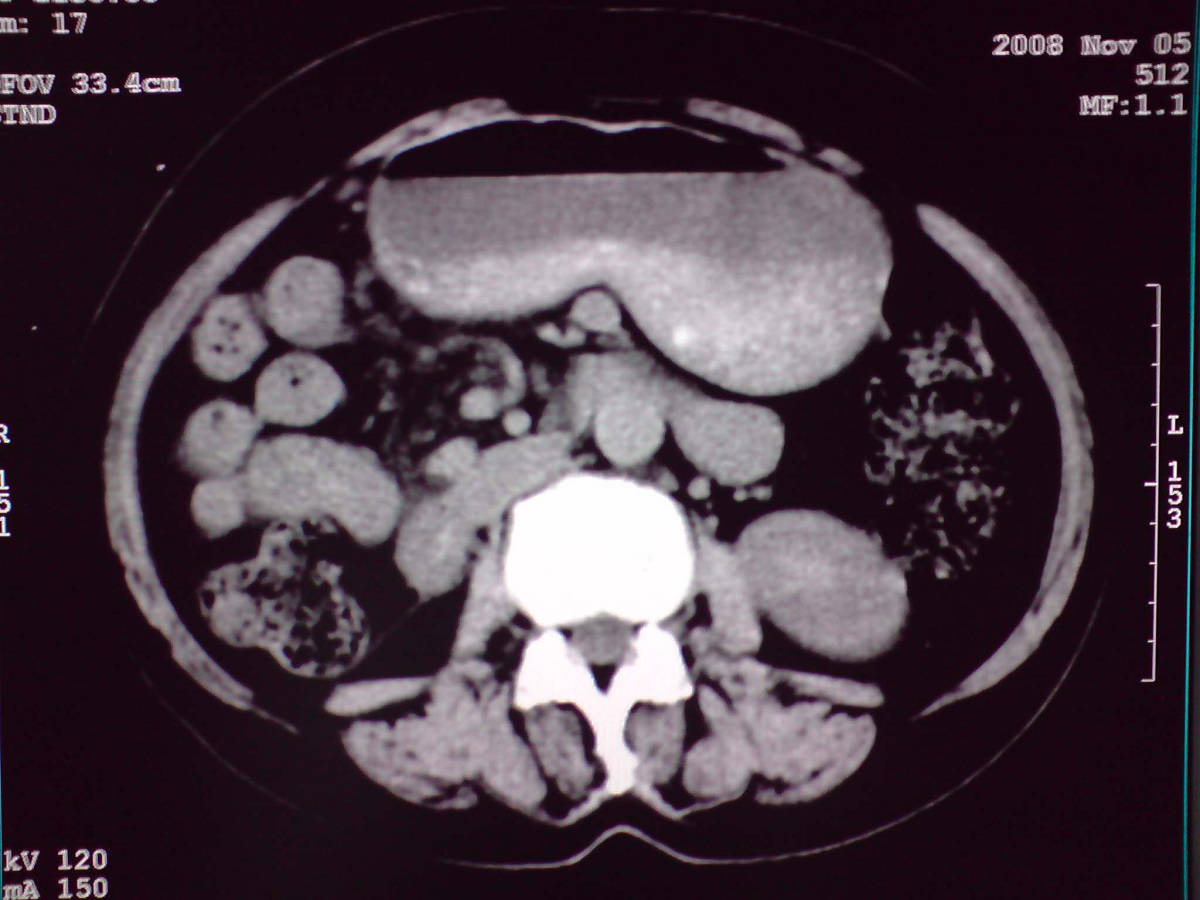

小网膜区见类圆形软组织密度肿块,密度不均,内见不规则低密度区,与肝左叶分界模糊,肝脏体积缩小,密度不均匀,边缘呈波浪状,尾状叶明显增大,脾脏下缘明显超出肝脏下缘。

肝脏比例失调,形态失常,外缘呈波浪状,腹腔内肿块内见低密度区并与肝脏界限欠清

1 肝脏各叶比例失调,形态失常,外缘呈波浪状。右叶萎缩,左叶 尾叶增大。2 腹腔内软组织密度肿块,低于肝实质密度,内见低密度区,并与肝脏界限欠清。腹膜后见肿大淋巴结,并与腹腔肿块关系密切。3 左肺下叶肿块,见边缘毛刺征及胸膜凹陷征,并与近肺门侧见异常血管相连。

肝脏比例失调,形态失常,外缘呈波浪状,腹腔内

小网膜区肿块内见低密度区并与肝脏界限欠清

1肝胃韧带区域一肿块,肿块上缘与肝左叶相连。肝硬化。考虑肝外生型肝癌可能性大,不除外间质瘤。2左肺下叶背段一结节,有偏心性空洞,长毛刺,其周有多发小结节。考虑结核可能性大。